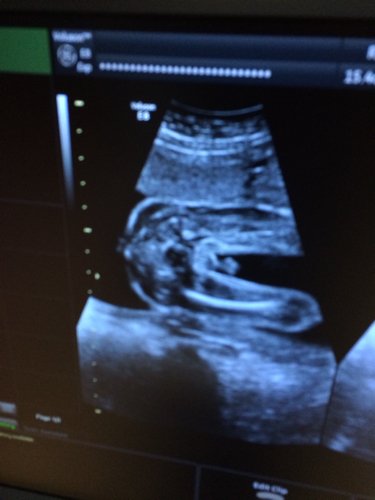

有没有会看宝宝彩超的呀?是女宝还是男宝?好好奇 点击展开 匿名用户 2015-07-08 15:02 为您推荐: 其他回答 这样看不出来的,只是猜猜而已,如果你真的那么想看到的话可以花点钱到外面那些小诊所里面去照祝你和你的宝宝身体健康! 匿名用户 2015-07-08 15:06 vvhjbh 匿名用户 2015-07-08 15:03 相关问题 看看我的宝宝,今天做的四维彩超,第一胎,能看出来是男宝还是女宝吗?好奇呀 这个月2号做的彩超报告,我的宝宝好么? 25周做四维彩超会不会 宝宝会更清晰…那个时间最好